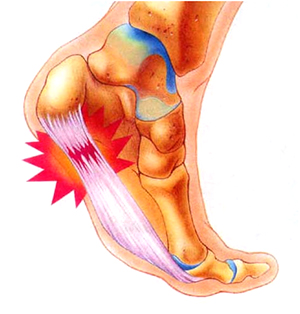

플랜타르 패시아염 (족저근막염)

- 발바닥의 아치에 위치한 두꺼운 섬유 조직인 족저근막이 염증이 생기는 질환입니다. 주로 장시간 서 있거나 걷는 경우, 혹은 비만으로 인해 과도한 압력이 가해져 발생합니다. 통증은 주로 아침에 일어났을 때 첫 발을 내딛을 때 가장 심하게 느껴지며, 점차 운동 후에도 나타날 수 있습니다.